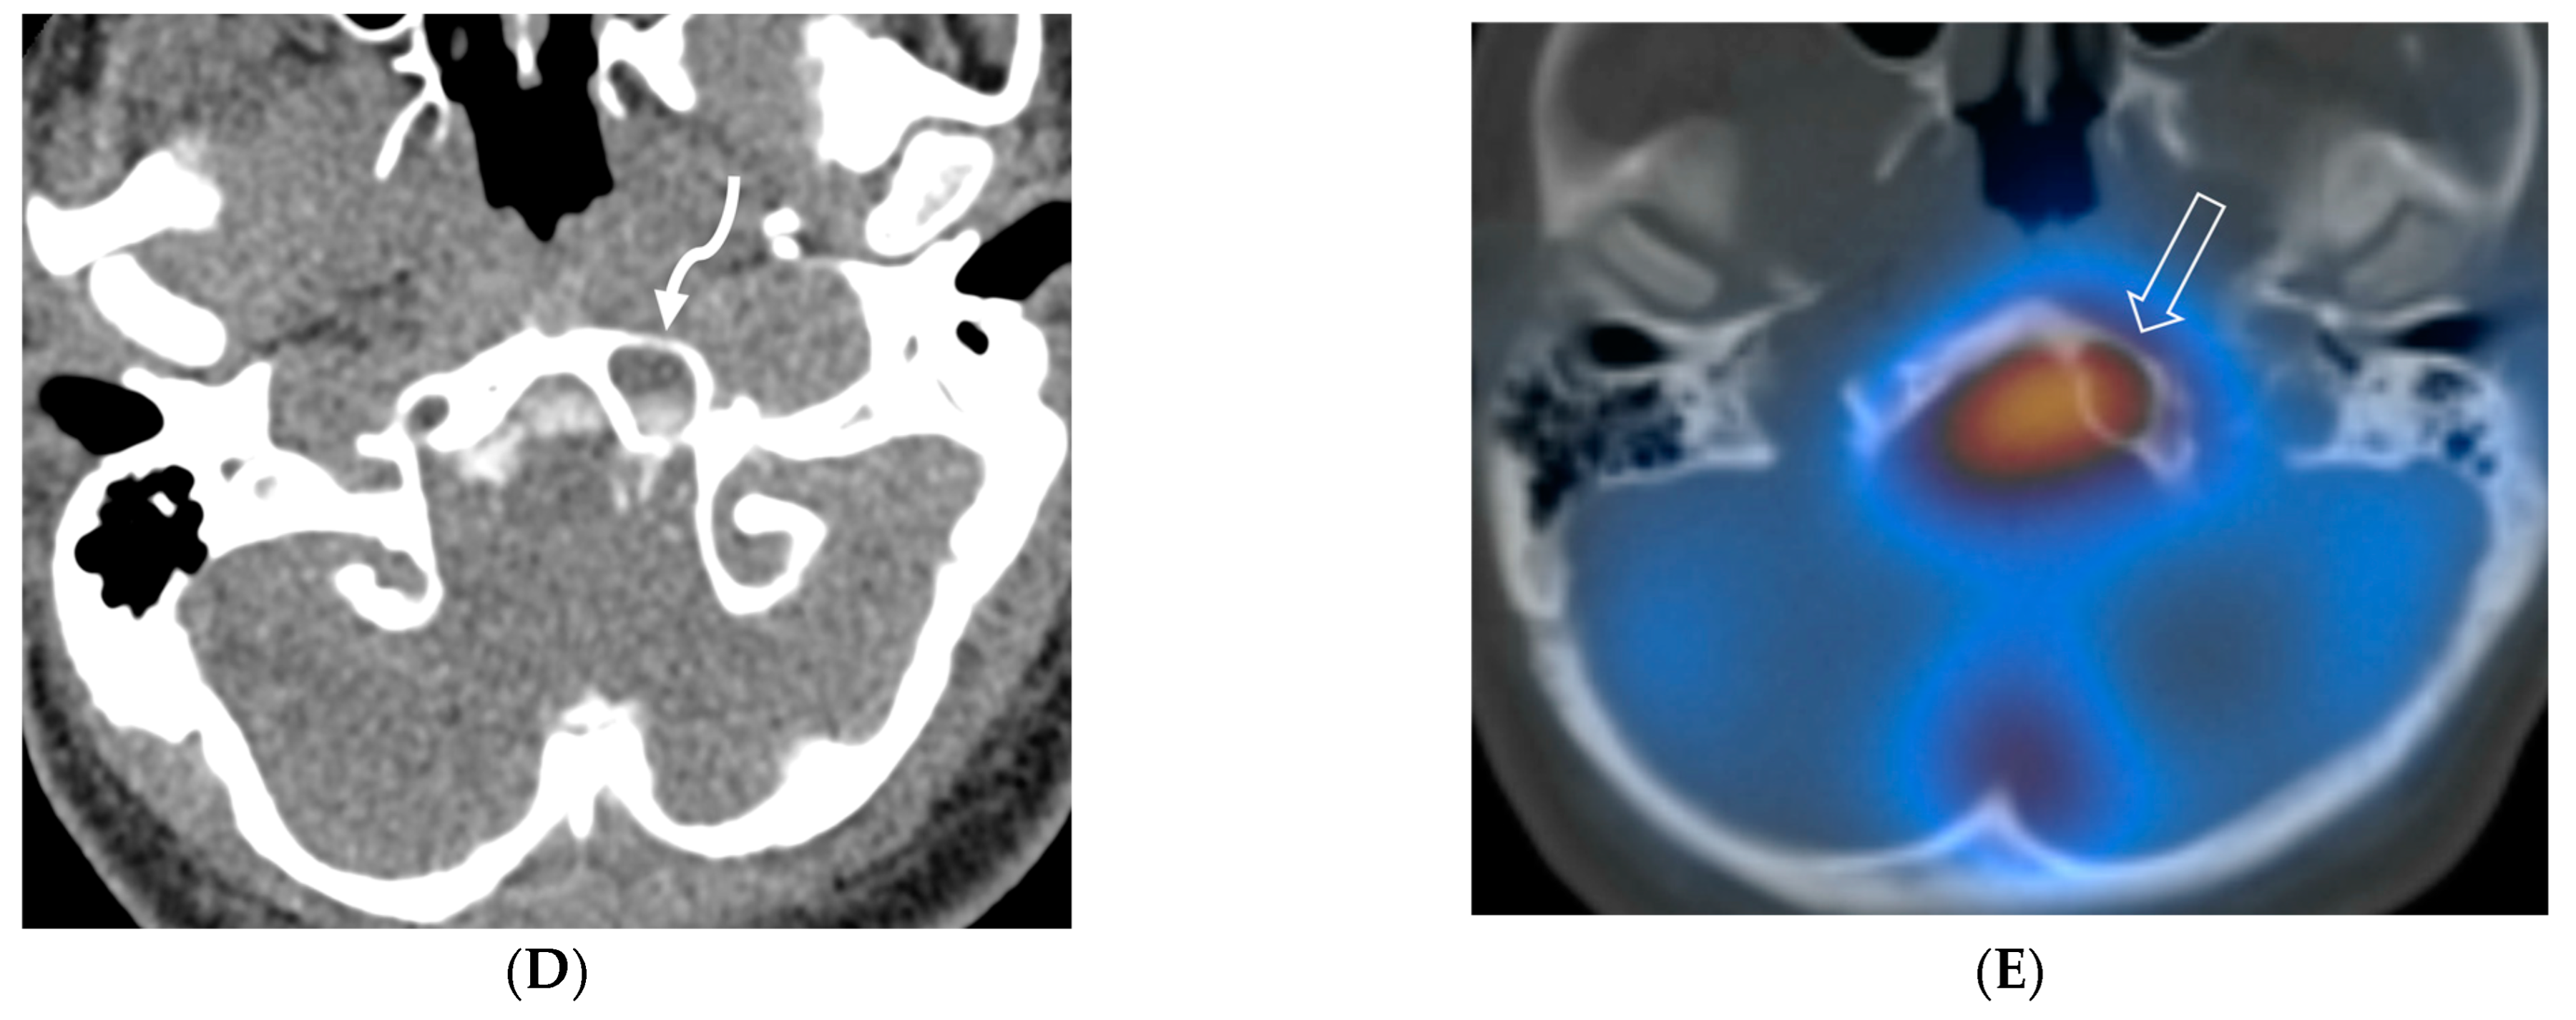

3.8. Intracranial Hypotension (IH)

Intracranial hypotension in children is frequently secondary to iatrogenic causes including lumbar punctures, craniospinal surgeries and ventricular shunt drain pressure changes [64]. Spontaneous causes are commonly connective tissue disorders such as Marfans and Ehler Danlos syndromes. Dural tears and meningeal diverticula have been demonstrated in these cases [65]. Beyond headaches, IH can manifest with nausea, vomiting, light sensitivity (photophobia), and stiff neck [66].

MRI features of IH can be explained by the Monroe-Kellie doctrine, which states that the intracerebral volume including blood, CSF and brain parenchyma remain the same. Thus, a decrease in CSF volume promotes dilatation and rounding of the venous sinuses, subdural fluid collections along with dural (pachymeningeal) enhancement which occurs due to vascular engorgement and transudation of fluid into it [67]. Hyperemia of the pituitary gland occurs which may mimic hyperplasia or pituitary tumor. Brainstem slumping or downward displacement of the brainstem, defined as red nuclei below the tentorium and low lying third ventricle below the sella, are highly specific indicators of IH, observed in half the cases. A pontomesencephalic angle of less than 50 degrees and mamillo pontine distance of less than 5.5 mm are sensitive and specific parameters to suggest IH [66].

With regard to spine imaging, in addition to the intracranial features of dural enhancement, venous engorgement and subdural collection, unique findings include meningeal diverticula, dural ectasia and C1–C2 sign (Figure 8 and Figure 9). Additionally, a CT myelogram may identify the precise location of the CSF leak which can be sealed off with a blood patch [65,68].

Figure 8.

Sagittal T1 (A), post axial T1 (B,C), axial CT myelogram (D) and technetium 99 m DTPA SPECT-CT (E): 16-year-old with Gorham’s disease. There is cerebellar tonsillar herniation and decrease in prepontine cisterns (white arrows). Significant increase in the size of the venous sinuses (dashed arrow). Diffuse pachymeningeal enhancement is seen (black arrows). Cystic-appearing foci at the skull base are in keeping with lymphangiomatosis with contrast pooling into the lytic lesion (curved arrow). Abnormal radiotracer extravasation in the left clival region correlating with lytic lesion (open arrow). Features are in keeping with intracranial hypotension secondary to CSF leak.